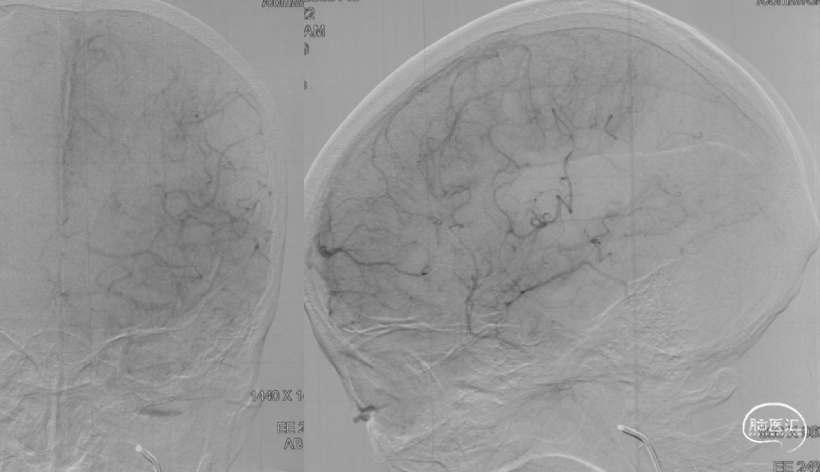

在NeuronMAX支撑下,微导丝/微导管辅助4MAX抽吸导管到位,进行抽吸。

抽吸一次,达到eTICI 2C再通。

● 本例患者采用的是抽吸取栓。与支架取栓相比,在器械成功到位的情况下,可能能够减少血管移位牵拉带来的出血风险。这例患者大脑中M2闭塞近端血管直径测量约1.6mm,4MAX导管远端外径4.3F(1.42mm),内径0.041''(1.04mm),能够实现远端到达和抽吸目的。